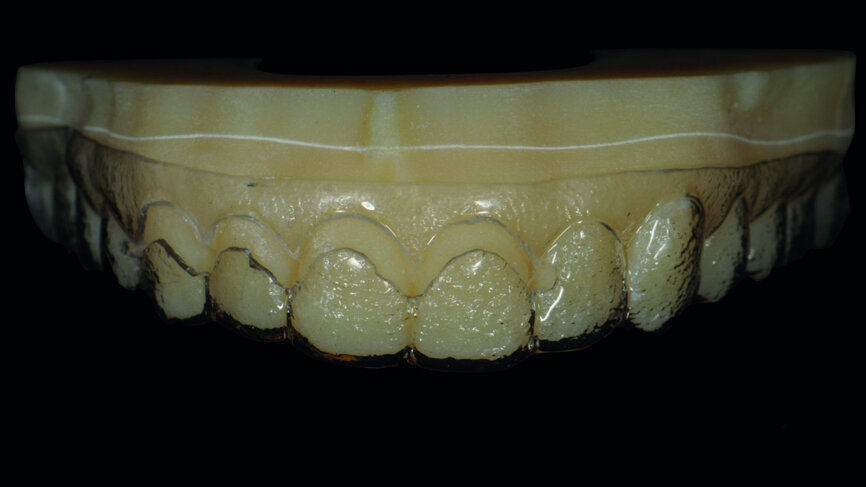

Fig. 12a: Digital planning of the provisional restorations.

Fig. 12b: Provisional restorations intraorally (Telio CAD).

Provisionalisation was executed digitally, using Telio CAD (Ivoclar Vivadent) in the Wieland Select CNC milling machine. The design was performed with the 3Shape DentalDesigner 2015 software (Figs. 12a & b). Two sets of final restorations were fabricated. The set of feldspathic veneers was fabricated on a stone model using IPS Style (Ivoclar Vivadent), while IPS Empress CAD Multi (Ivoclar Vivadent) was used for the digitalset (Figs. 13 & 14). Both sets were examined intraorally with a try-in paste to compare the optical properties of the feldspathic and the CAD/CAM veneers (Figs. 15a–c).